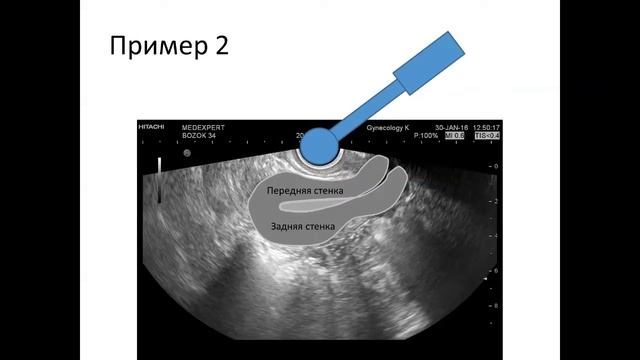

Практическое занятие: УЗИ органов малого таза у женщин (пациентка 1)

Практическое занятие для врачей курса первичной переподготовки по ультразвуковой диагностике в медицинском институте БФУ им. И.Канта (г. Калининград). Тема занятия: УЗИ органов малого таза у женщин